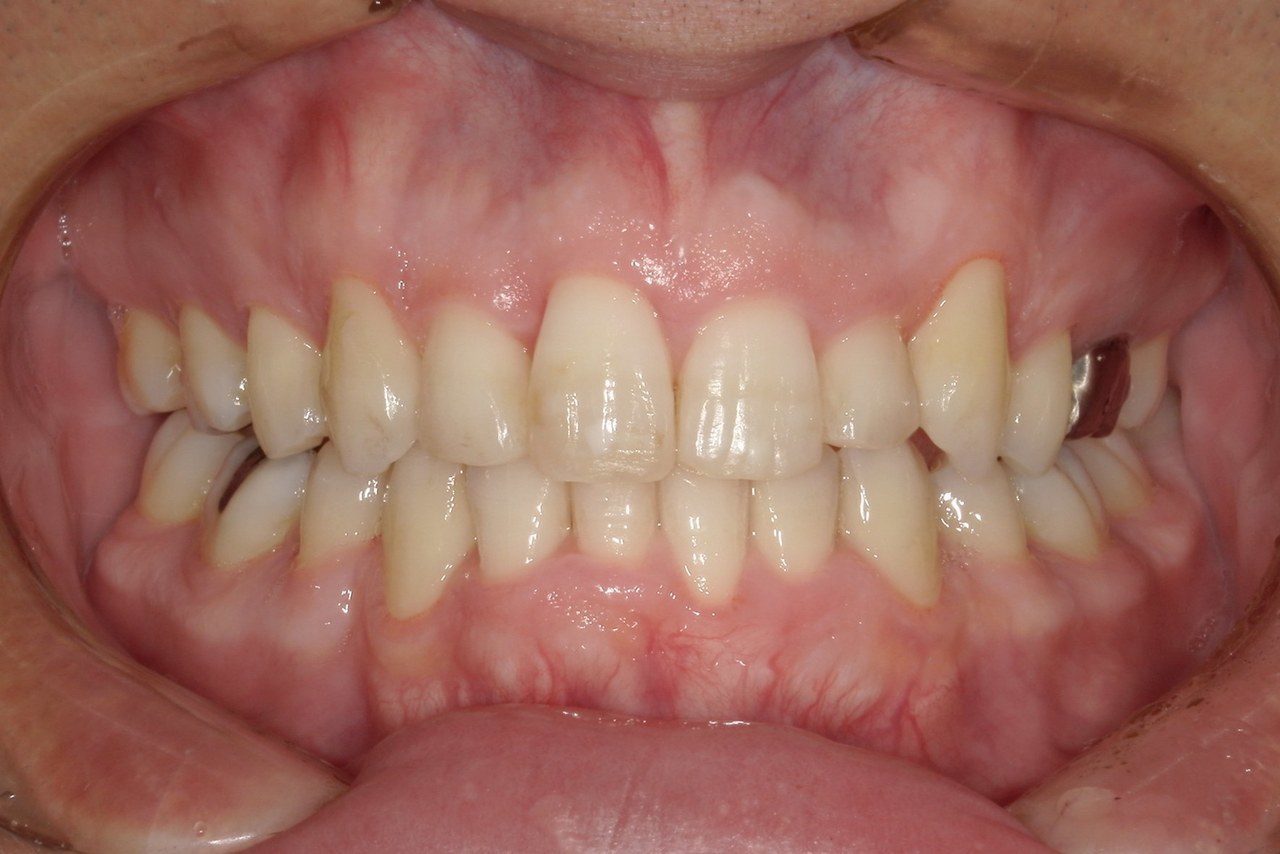

Before

浜松市中央区・自動車学校前駅のインビザラインの症例

K.M 20代女性

上の前歯が前方に出ていて横顔が気になるとの主訴でご来院。上下犬歯から犬歯までの6本が噛み合うよう、全体的に歯を内側に移動させることで、前歯の噛み合わせを整え叢生と開咬を治療しました。

​治療の期間:R5. 7/5〜R7. 1/17

​治療の価格:66万円